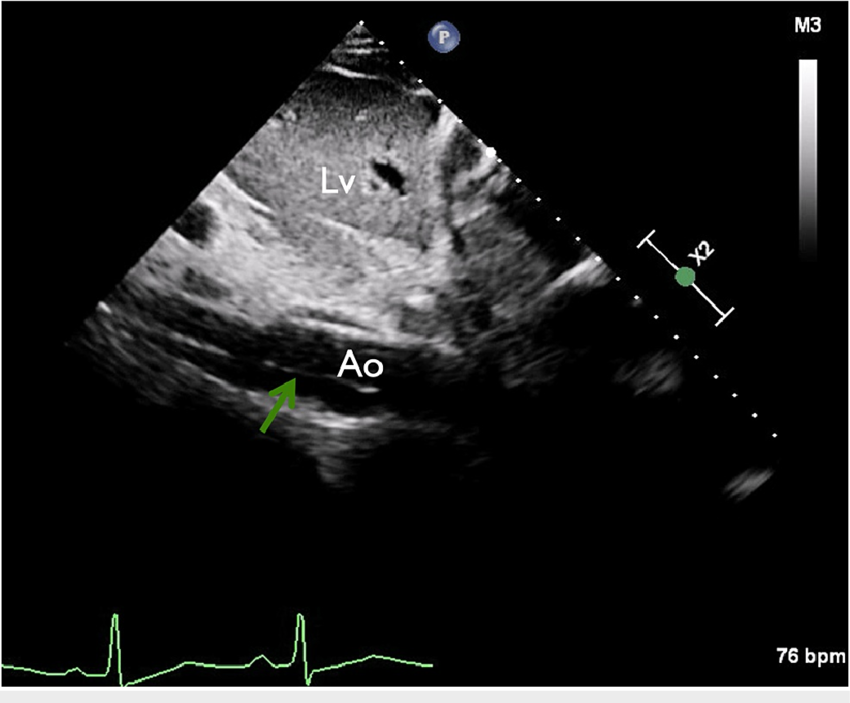

Draw and label the PSLAX.

Outline how to optimize the standard Parasternal echo views.

Correct alignment of the transducer on axis

Center the anatomy

Instrumentation settings (gain, focus, depth, etc.)

In an M-mode tracing of LV basal wall in PSLAX, list the measurements made and describe how to measure them

AoV

curser where the AoV leaflets close in diastole

aortic root diameter measured at end diastole from the tissue interface of the anterior wall of aortic root to posterior wall of aortic root

LA measured at end systole from the trailing tissue interface to posterior tissue interface

Name the measurements made in PSLAX and when they are made.

End-diastole:

Ao root

IVS diameter

LVIDd

PW diameter

End-systole:

LA diameter

LVIDs